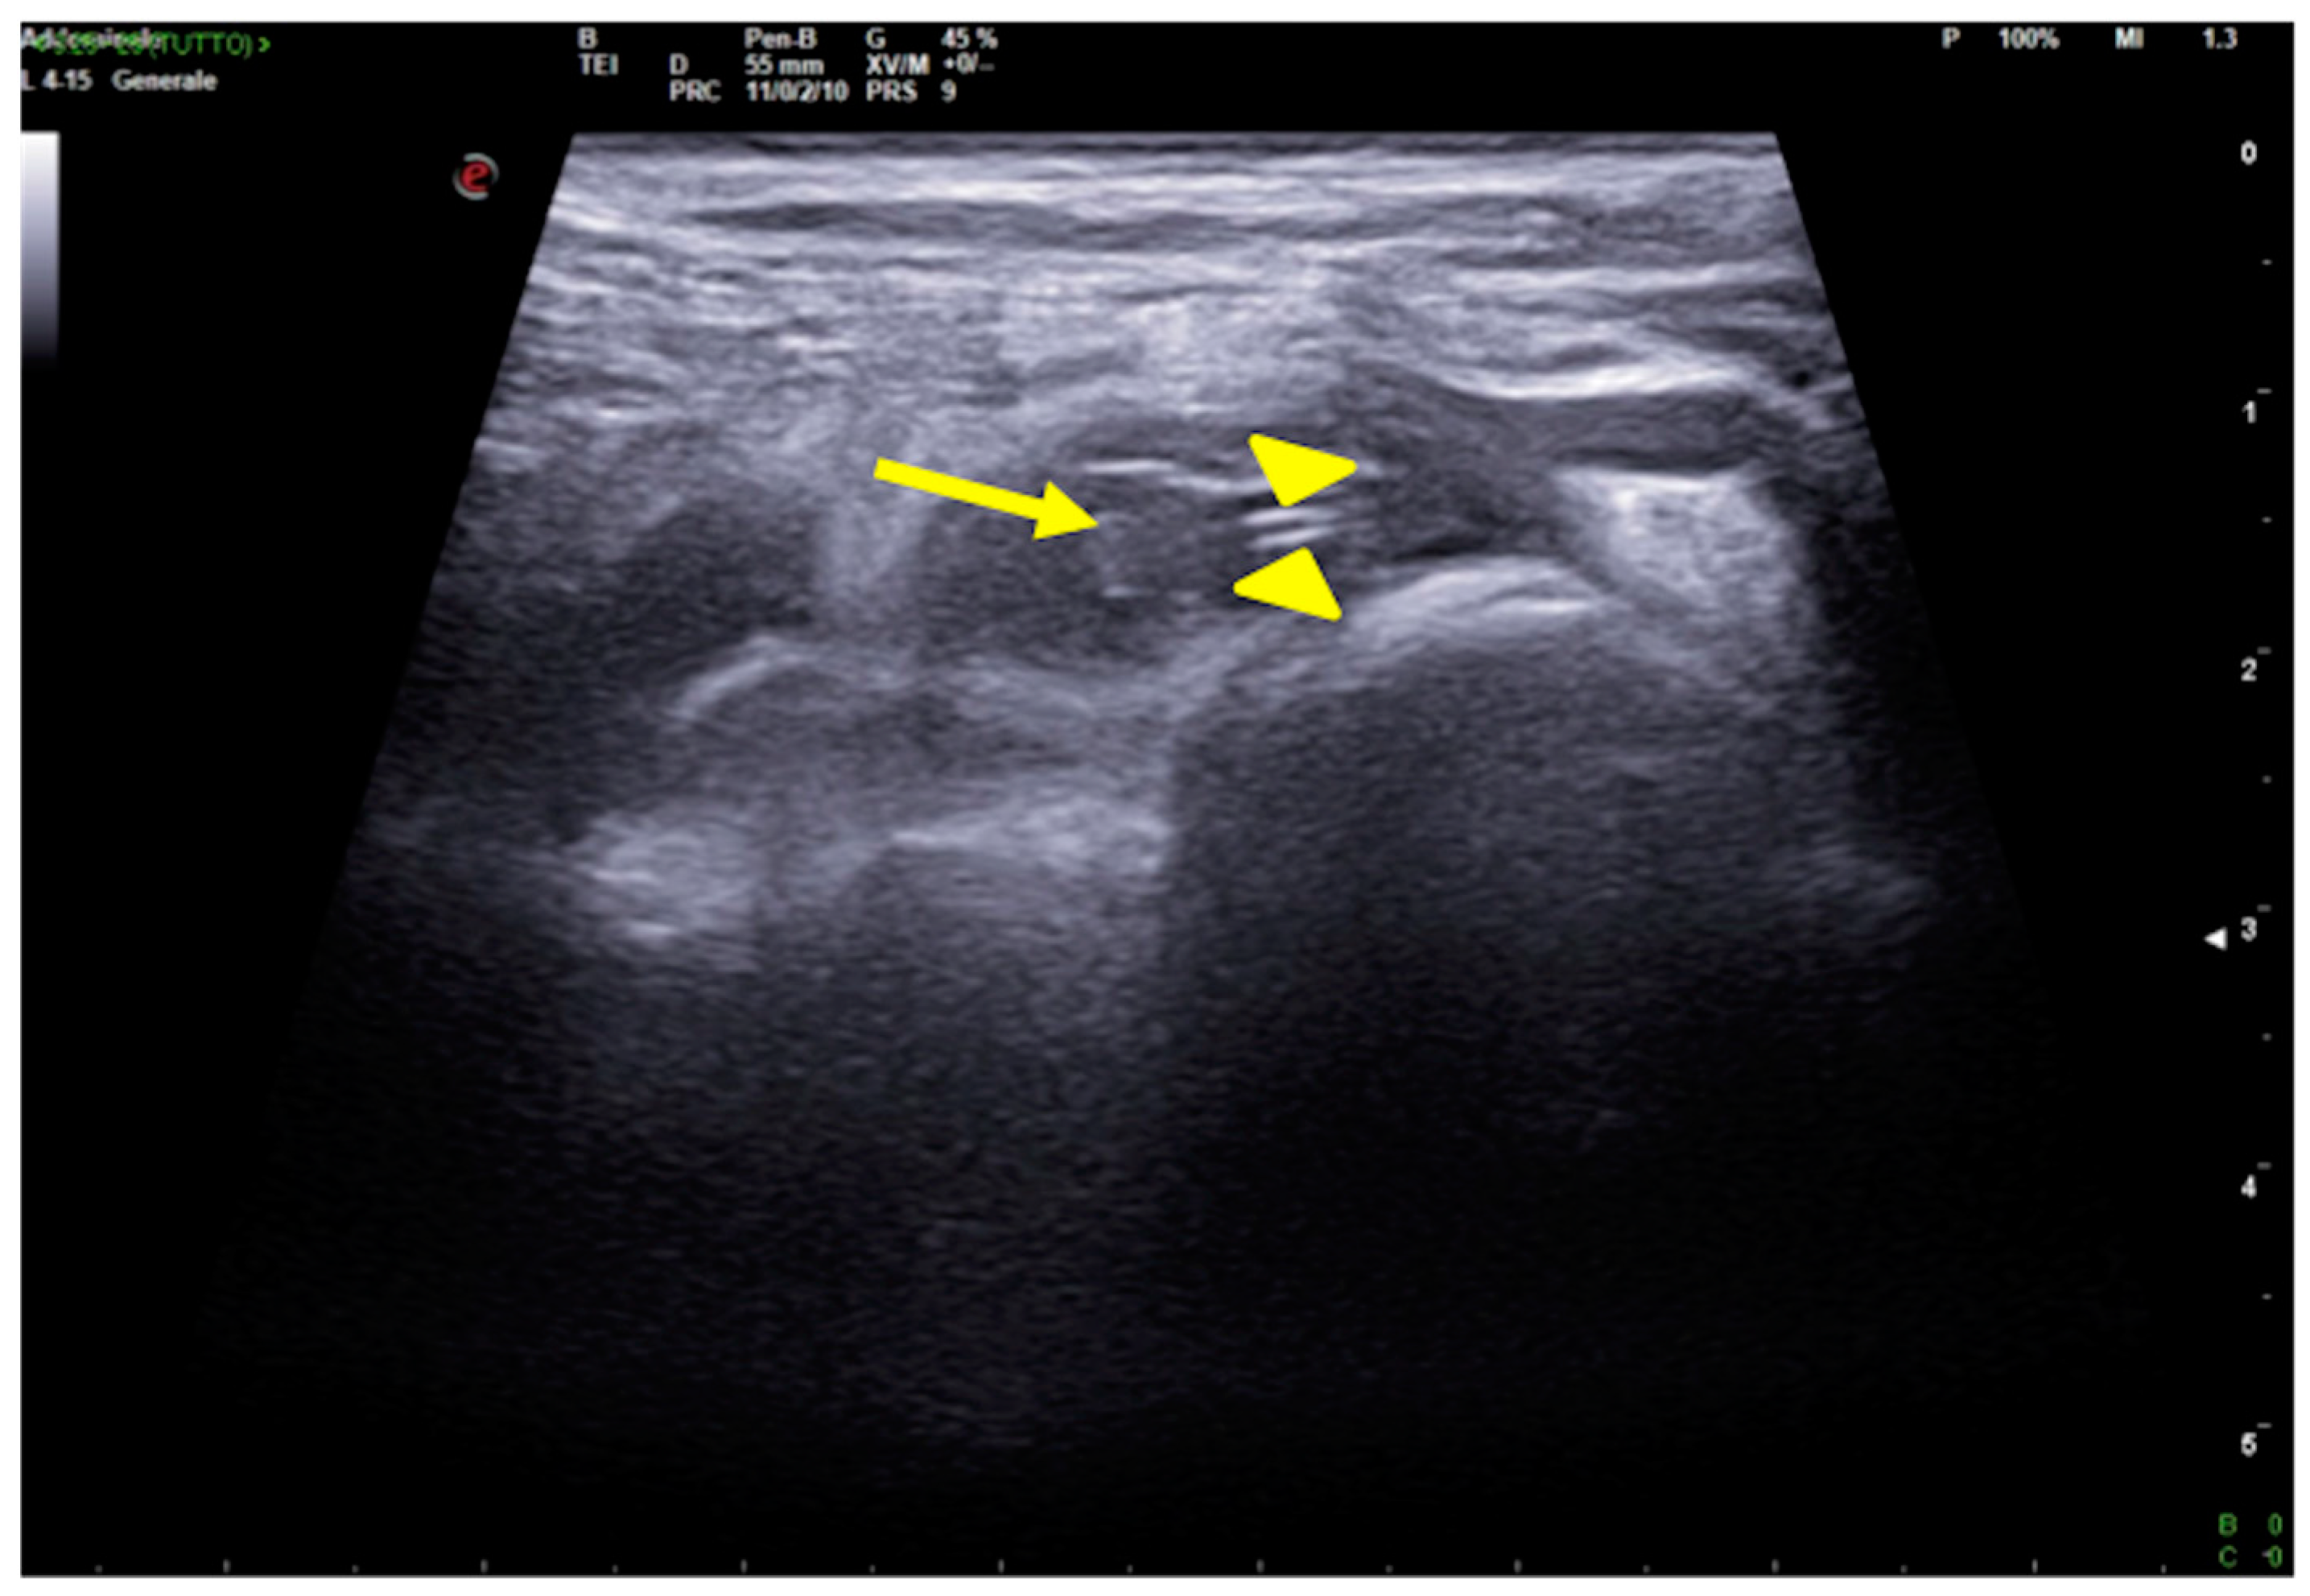

2.1. Atelectasis

- Lichtenstein, D.; Mezière, G.; Seitz, J. The The dynamic air bronchogram. A lung ultrasound sign of alveolar consolidation ruling out atelectasis. Chest 2009, 135, 1421–1425. [Google Scholar] [CrossRef]

- Lichtenstein, D.A.; Lascols, N.; Prin, S.; Mezière, G. The “lung pulse”: An early ultrasound sign of complete atelectasis. Intensiv. Care Med. 2003, 29, 2187–2192. [Google Scholar] [CrossRef]